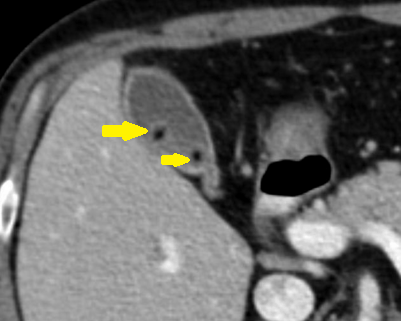

Şekilde kırmızı çizgi ile kalınlığı yaklaşık 2 cm olan perikolesistik sıvı görülmekte. safra kesesi duvarının konstrast tuttuğu görülüyor. Yer yer duvarın devamlılığının bozulması perforasyon olarak algılanmamalı. Ödemli yapıda kontrast görünümü yer yer kesiliyor. Sarı okla görülen bölümde ise safra kesesi duvarının kontrast tuttuğu görülüyor. Bu bulgular akut kolesistit ile uyumlu.